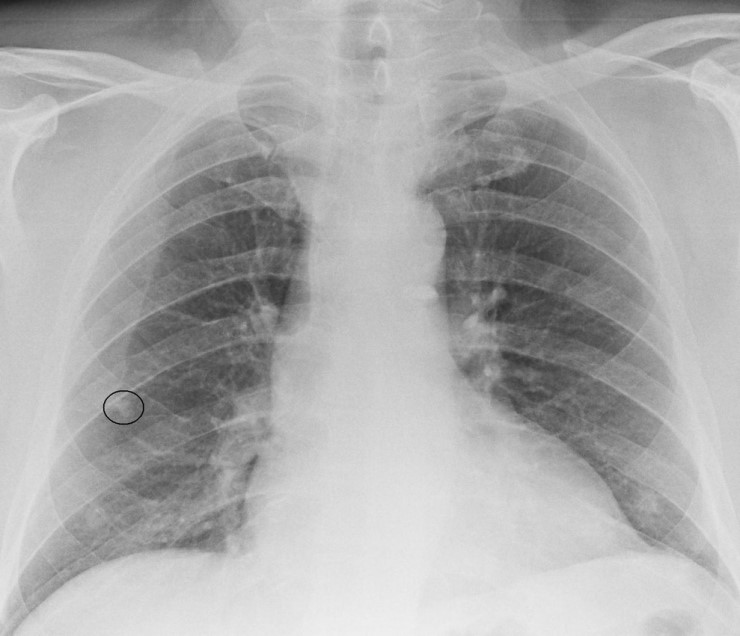

Rib Bone Island . Bone island, also known as enostosis, is a benign bone lesion commonly found on radiographs. They sometimes resemble other types of lesions. • asymptomatic focal areas of bony sclerosis. A bone island, also known as an enostosis, is a focus of compact bone located in cancellous bone (see the images below). Bone islands are lesions which are composed of dense bone within another bone in your body. A bone island is a harmless piece of compact bone inside cancellous bone. It appears as a small, circular, opaque area within. They are round and small (2 to 20 mm) intramedullary. Bone islands, previously known as enostoses, are common benign sclerotic bone lesions that usually represent an incidental finding. Bone islands almost never cause. You might need a biopsy if it causes pain. This is a benign entity that is usually found. Bone island, also called an enostosis, is a benign bone tumor mostly encountered as an incidental and asymptomatic finding.

Rib Bone Island A bone island is a harmless piece of compact bone inside cancellous bone. Bone island, also called an enostosis, is a benign bone tumor mostly encountered as an incidental and asymptomatic finding. You might need a biopsy if it causes pain. Bone islands almost never cause. Bone islands, previously known as enostoses, are common benign sclerotic bone lesions that usually represent an incidental finding. A bone island, also known as an enostosis, is a focus of compact bone located in cancellous bone (see the images below). It appears as a small, circular, opaque area within. They are round and small (2 to 20 mm) intramedullary. • asymptomatic focal areas of bony sclerosis. Bone islands are lesions which are composed of dense bone within another bone in your body. This is a benign entity that is usually found. Bone island, also known as enostosis, is a benign bone lesion commonly found on radiographs. They sometimes resemble other types of lesions. A bone island is a harmless piece of compact bone inside cancellous bone.

An enostosis (pl. enostoses, also known as a "bone island") is a common Rib Bone Island A bone island is a harmless piece of compact bone inside cancellous bone. It appears as a small, circular, opaque area within. Bone islands almost never cause. They sometimes resemble other types of lesions. • asymptomatic focal areas of bony sclerosis. Bone island, also known as enostosis, is a benign bone lesion commonly found on radiographs. Bone islands, previously known. Rib Bone Island.

Bone Island Radiology Key Rib Bone Island Bone islands, previously known as enostoses, are common benign sclerotic bone lesions that usually represent an incidental finding. Bone island, also called an enostosis, is a benign bone tumor mostly encountered as an incidental and asymptomatic finding. Bone island, also known as enostosis, is a benign bone lesion commonly found on radiographs. This is a benign entity that is usually. Rib Bone Island.